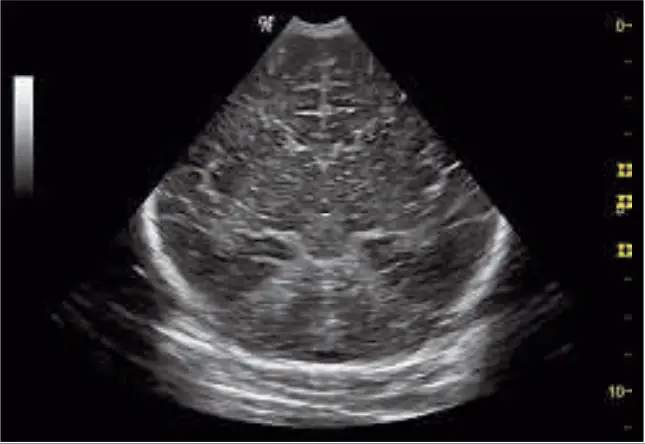

| Sagittal prostate showing cystic structure imaging with the E8CS probes using fundamental imaging and SRI | Apical four-chamber view of the adult heart with color Doppler using the 3S probe |

Introducing LOGIQ® P6. Its combination of performance and versatility enables you to meet the needs of patients across multiple clinical settings. With advanced detail resolution and color flow, you can easily distinguish between cystic and solid lesions, especially in small areas like the thyroid, breast, and ovary. And the increased detail and contrast resolution help identify even the most challenging pathologies. These capabilities help to optimize your ability for earlier diagnosis.

Speckle Reduction Imaging (SRI). Heighten your visibility of organs and lesions with high-definition contrast resolution that suppresses speckle artifacts while maintaining true tissue architecture.

Harmonics. Increase resolution and cystic clarity with a combination of coded harmonics and Phase Inversion Harmonics.